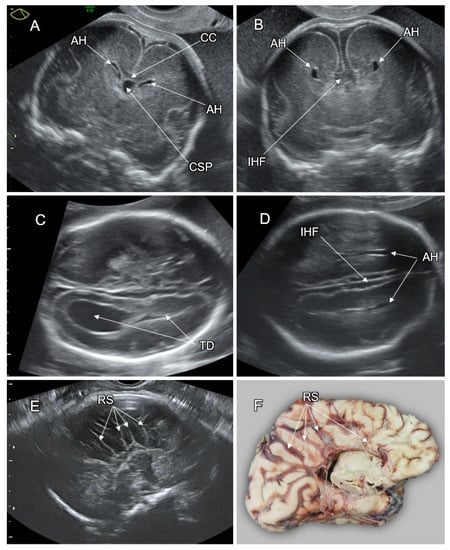

5. Disorders of the Corpus Callosum (DCC)

- Paul, L.K.; Brown, W.S. Agenesis of the corpus callosum: Genetics, developmental and functional aspects of connectivity. Nat. Rev. Neurosci. 2007, 8, 287–299. [Google Scholar] [CrossRef]

- Edwards, T.J.; Sherr, E.H. Clinical, genetic and imaging findings identify new causes for corpus callosum development syndromes. Brain 2014, 137, 1579–1613. [Google Scholar] [CrossRef]

- Leombroni, M.; Khalil, A. Fetal midline anomalies: Diagnosis and counselling Part 1: Corpus callosum anomalies. Eur. J. Paediatr. Neurol. 2018, 22, 951–962. [Google Scholar] [CrossRef]